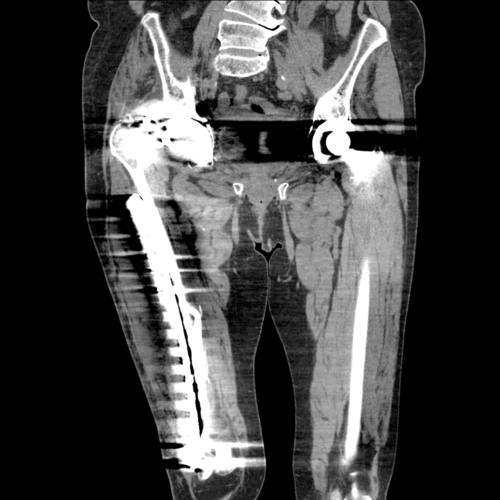

A pre-operative scannogram demonstrating the dislocation of the right implant from the constrained acetabular liner

Pre-operative cross sectional imaging demonstrates the extent of the intrapelvic migration